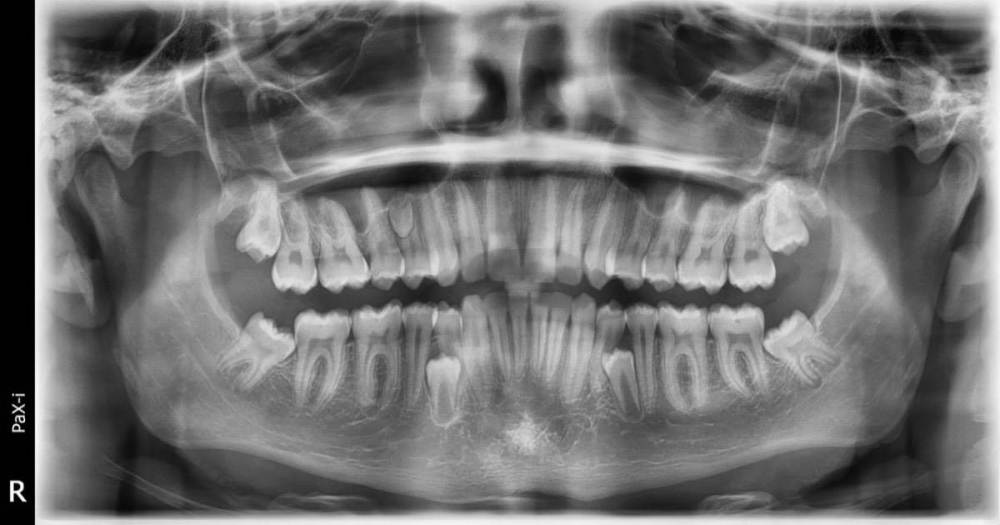

Всем привет! Сын (17 лет) обратился к ортодонту с жалобой на минимальную неровность верхних единичек. Ортодонт сказал - прикус норм, дефект минимальный. А на панорамном снимке вот такое. Что с этим делать. Ортодонт сказал - ничего, все нормально, крайне редкое явление. Они ж не вырастут? И не убьют корни имеющихся зубов. У сына визуально ровный зубной ряд.